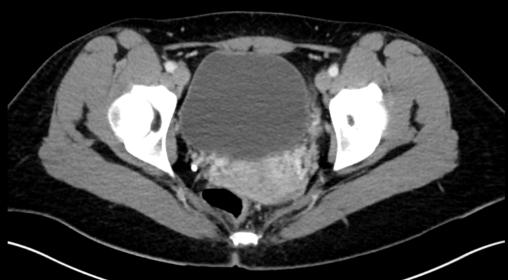

Calcul pelvien droit sans mesure

Scanner abdominopelvien non injecté.